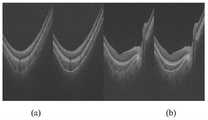

The corresponding images in fig. 4 are: (a) and (b) the segmentation results of the transverse scan images of the normal human eye without optic disc and with optic disc respectively (c) and (d) the segmentation results of the transverse scan images of the pathologic myopic human eye without optic disc and with optic disc respectively (e) and (f) the segmentation results of the transverse scan images of the pathologic myopic human eye with other diseases respectively.

As can be seen from fig. 4, the network model predicted the segmentation map is more accurate for both normal and pathologically myopic choroids, and for choroids that do not contain regions of ONH and for choroids that contain regions of ONH. And comparing the segmentation result of the choroid of the test set predicted by the network model with a gold standard marked by a doctor, and adopting a relative upper boundary error, a relative lower boundary error, a thickness error and a dess coefficient as objective indexes of the evaluation method. Wherein the calculation formula of the dess coefficient is as follows: